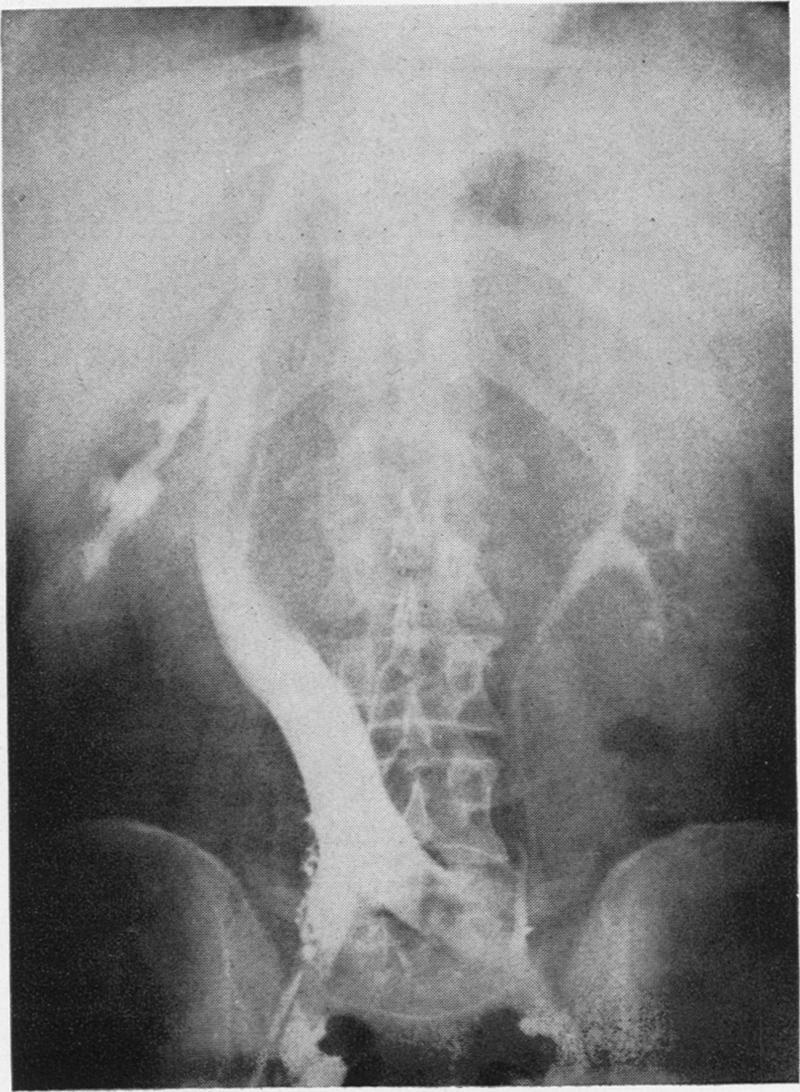

Visualization of the inferior vena cava as an adjunct to diagnosis of retroperitoneal tumors, a case report.

Ann Surg. 1954 Dec;140(6):892-6. doi: 10.1097/00000658-195412000-00016.